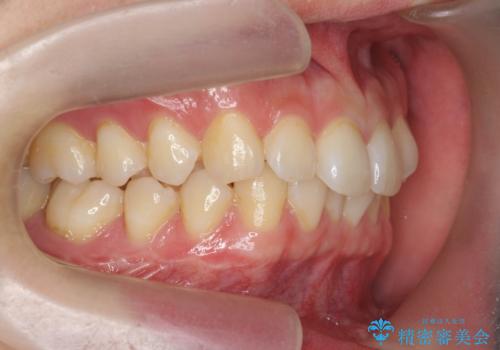

- 20代男性

- ワイヤー

- 10ヶ月

- 取り外しの必要なマウスピース矯正ではなくワイヤー矯正を希望され来院されました。

マウスピース矯正、ワイヤー矯正どちらの方法でも治療は可能ですが、ご要望の通りワイヤー矯正で歯の排列を行っていきます。